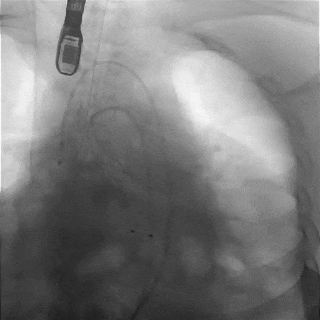

主动脉根部造影

TF29瓣膜,0位定位释放

瓣膜稳定释放至全展开

造影观察:瓣膜位置可,形态佳

左冠切线观察,瓣膜位置可

冠脉灌注良好

缓慢脱钩,瓣膜无位移

脱钩后造影

瓣膜位置可,无瓣周漏

外周造影检查,血管无损伤